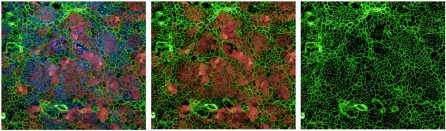

Using the Opera Phenix, NYSCF scientists are tracking the growth of tumor organoids — living avatars of patient tumors created with the power of stem cells. No two tumors are the same, and this image shows organoids colored to categorize different characteristics.

NYSCF scientists use these patient-specific organoids to improve the way women’s reproductive cancers are studied and to develop personalized treatments as part of our Women’s Reproductive Cancers Initiative.

“The Opera Phenix has allowed us to scale up our characterization and analysis of these unique models, illuminating the heterogeneity of the disease. Looking at different organoids across patients, as seen in the second photo, shows how the disease can manifest in variable ways, and grouping them helps scientists understand which types of patients are developing which disease features,” explained Laura Andres-Martin, PhD, a Research Investigator in Oncology who leads the Initiative.